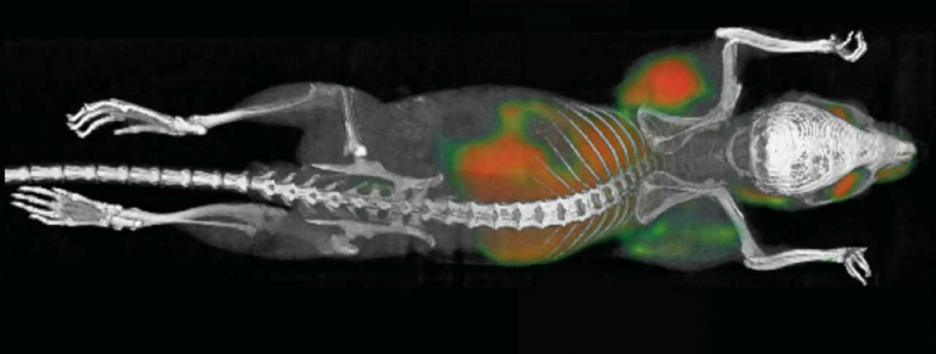

Будущее

Инъекция помогла иммунной системе уничтожить раковые опухоли у мышей. Люди на очереди